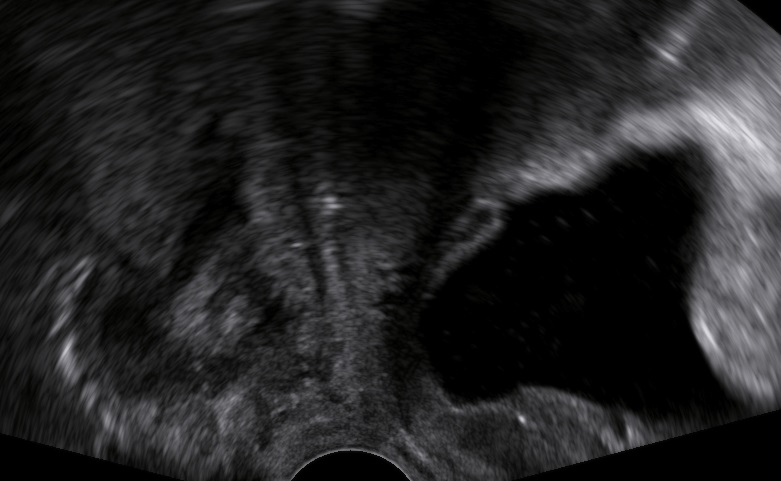

Types of cystocele:

Symptoms of anterior vaginal wall prolapse like incomplete bladder emptying or feeling of vaginal bulge are frequent when:

- The bladder descends at least 10mm below the symphysis pubis (pelvic floor sonography).